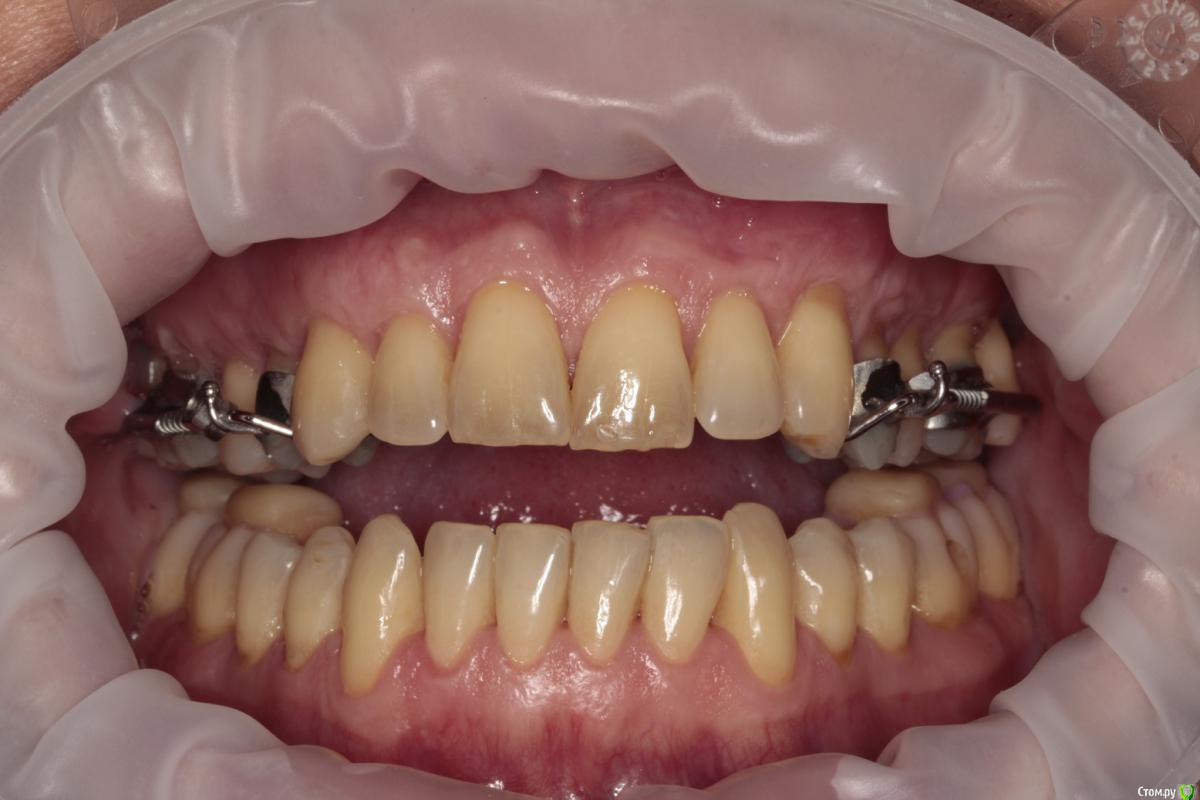

1. рецессии, клиновидный дефект, ВНЧС в результате неправильного прикуса (макрогнатия нижней и микрогнатия верхней челюсти)

2. год назад у меня был гингивит, переросший в некроз, приведший к полной потере сосочков нижней челюсти

3. сейчас уже пол года мы увеличиваем в длину верхнюю челюсть, что бы наконец устранить причину всего. Потом будем брекетами выпрямлять все оставшееся.

так же мы понимаем, что сосочки это не только эстетика, но и важный функционал всей системы. И без них жить нельзя. При этом, технологии их восстановления, после некроза, не существует.

сосочки утеряны вследствие пародонтита. Восстановить их почти нереально. Только ортопедически, изменив форму зубов.